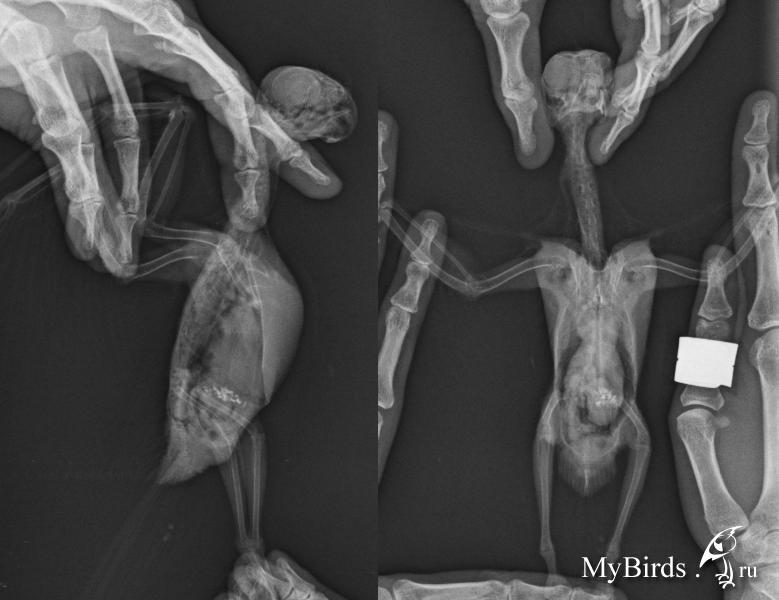

Добрый день! Около Месяца назад дочка прищемила кореллу дверью ( в районе шеи тк там все перья вылетели) , когда он вылетал из ее комнаты. Он упал с высоты 1,5 метра и больше не летает, сначала лежал, потом ползал, потом начал немного сидеть на хвосте, сейчас ходит понемногу, но его почему то закидывает вперед и направо. Сходила в клинику к орнитологу, сделали рентген, позвоночник в порядке, внутренние органы тоже, была затемнена правая сторона ГМ. Назначили лечение: Церебролизин по 0,1 м 2 раза в день -30 дней; витамины В1,6,12 чередовать в течении 30 дней; кальций через день всего 5 раз и еще таблетка на М ( забыла название), неделю давала. Меня беспокои то что он при быстрой хотьбе заваливается в перед и направый бок, летать понятно что я пока от него не жду. Может кто подскажет правильно ли лечение, и почему он заваливается?! Рентген прикрепила.